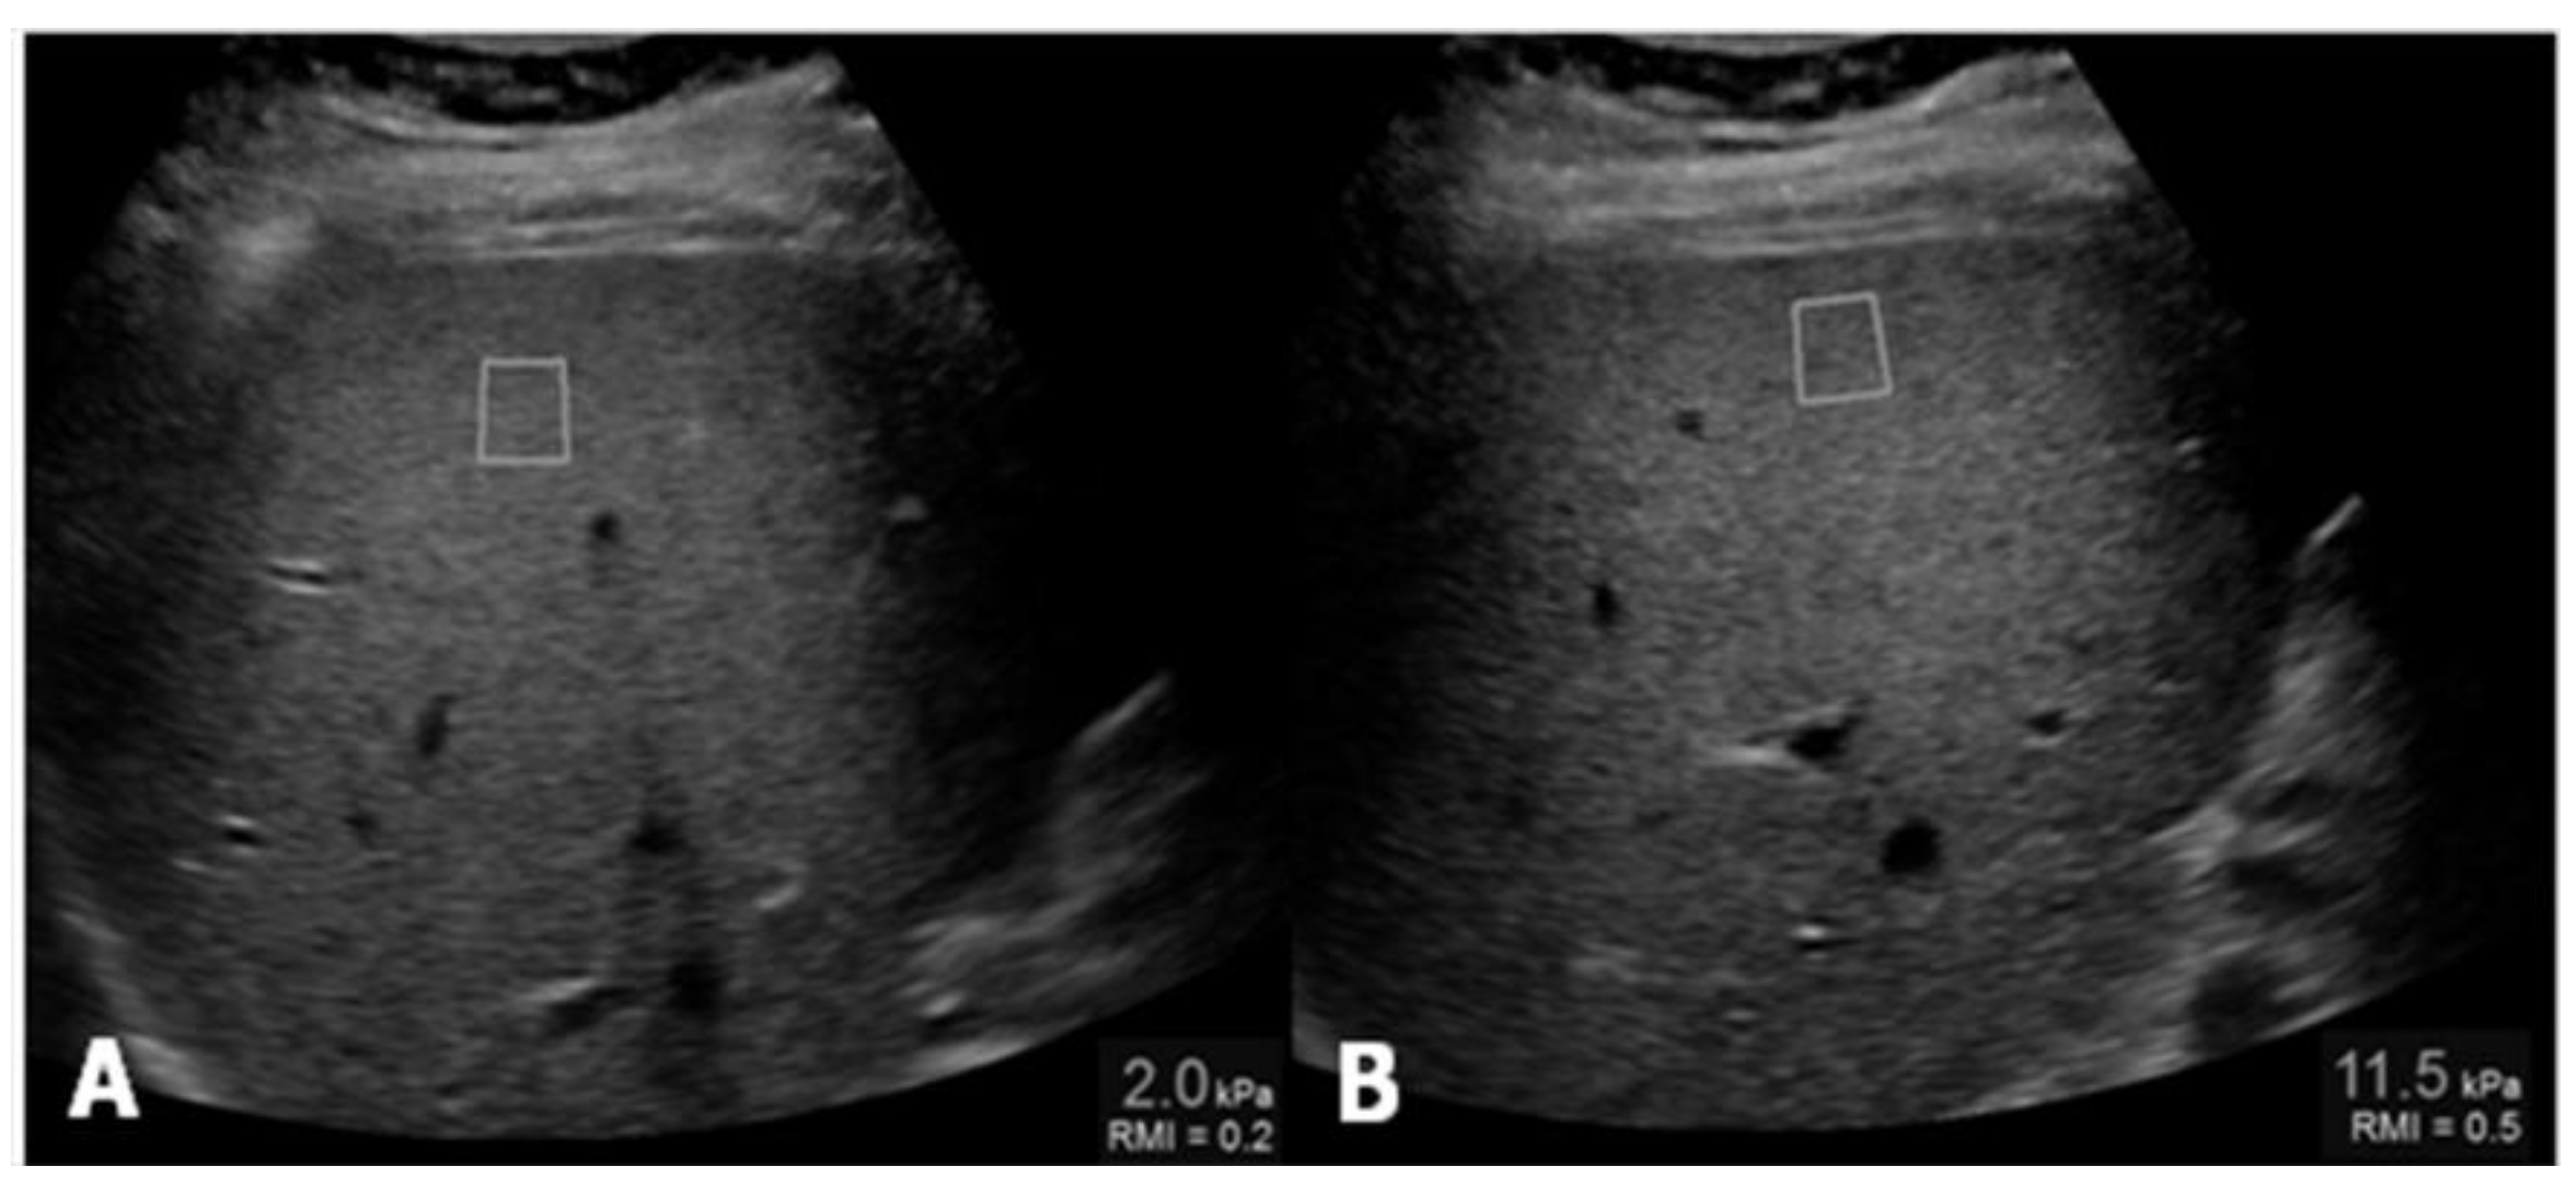

Ultrasound Elastography